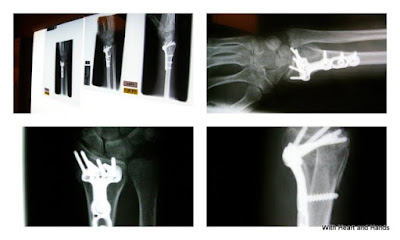

little did i know, that my new bionic parts of titanium plate and screws,

would look exactly like an implanted, alien hand.